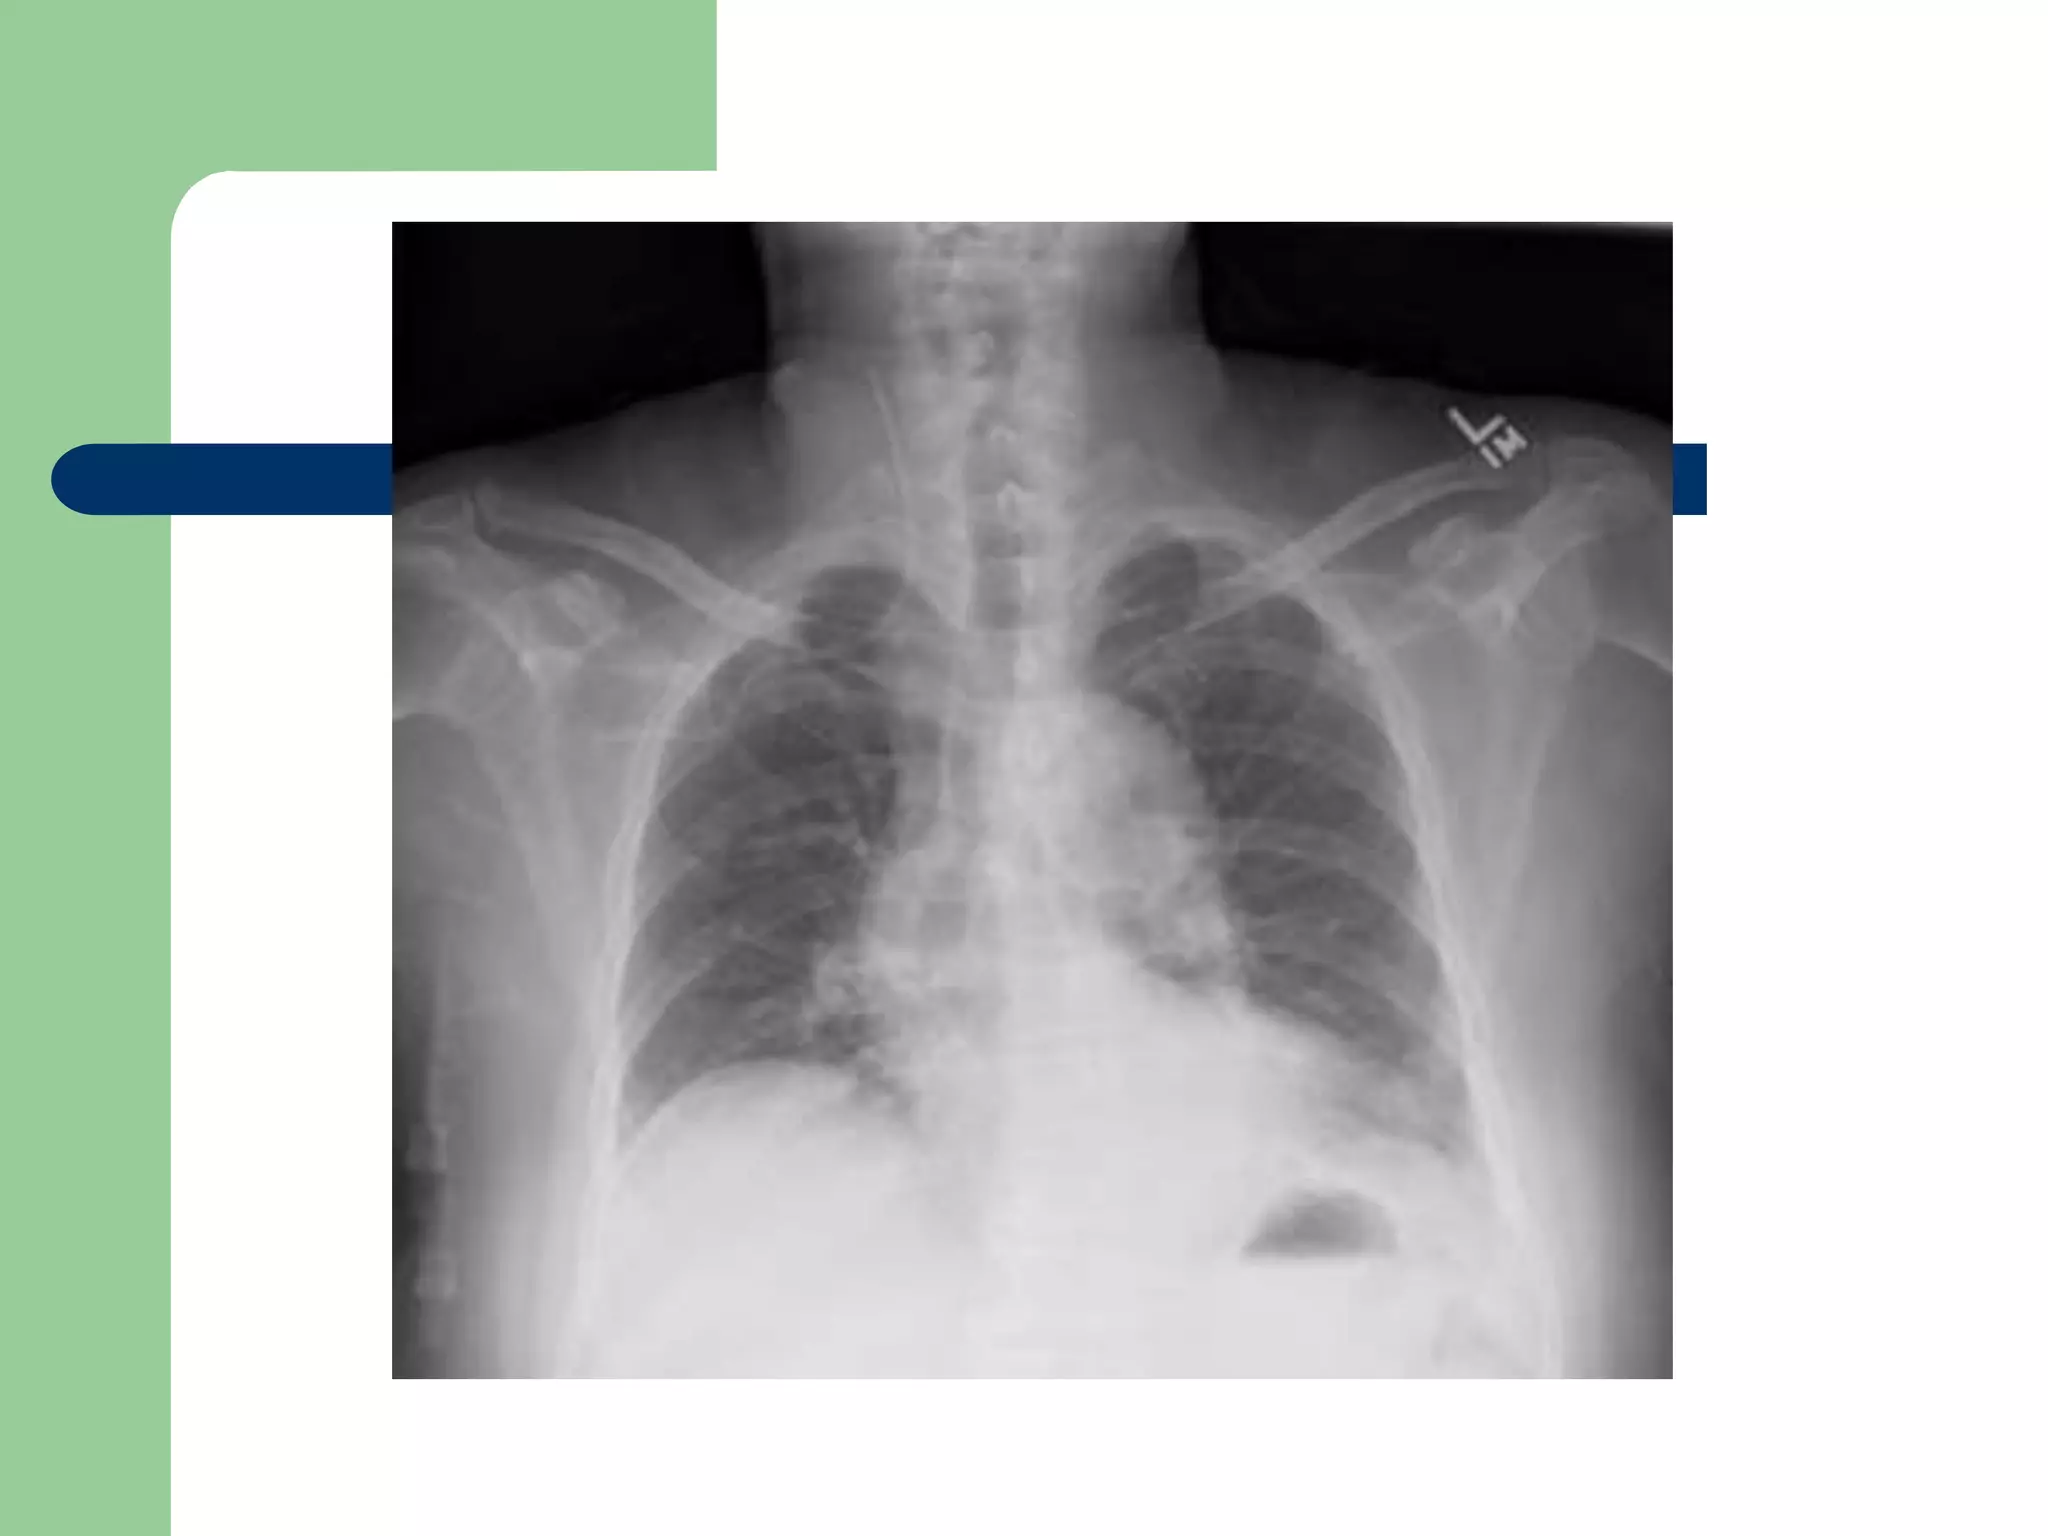

Correct IJ placement

CXR provided by Jeremy P. Feldman, MD

E-Bay Fellow in Pulmonary Vascular Disease